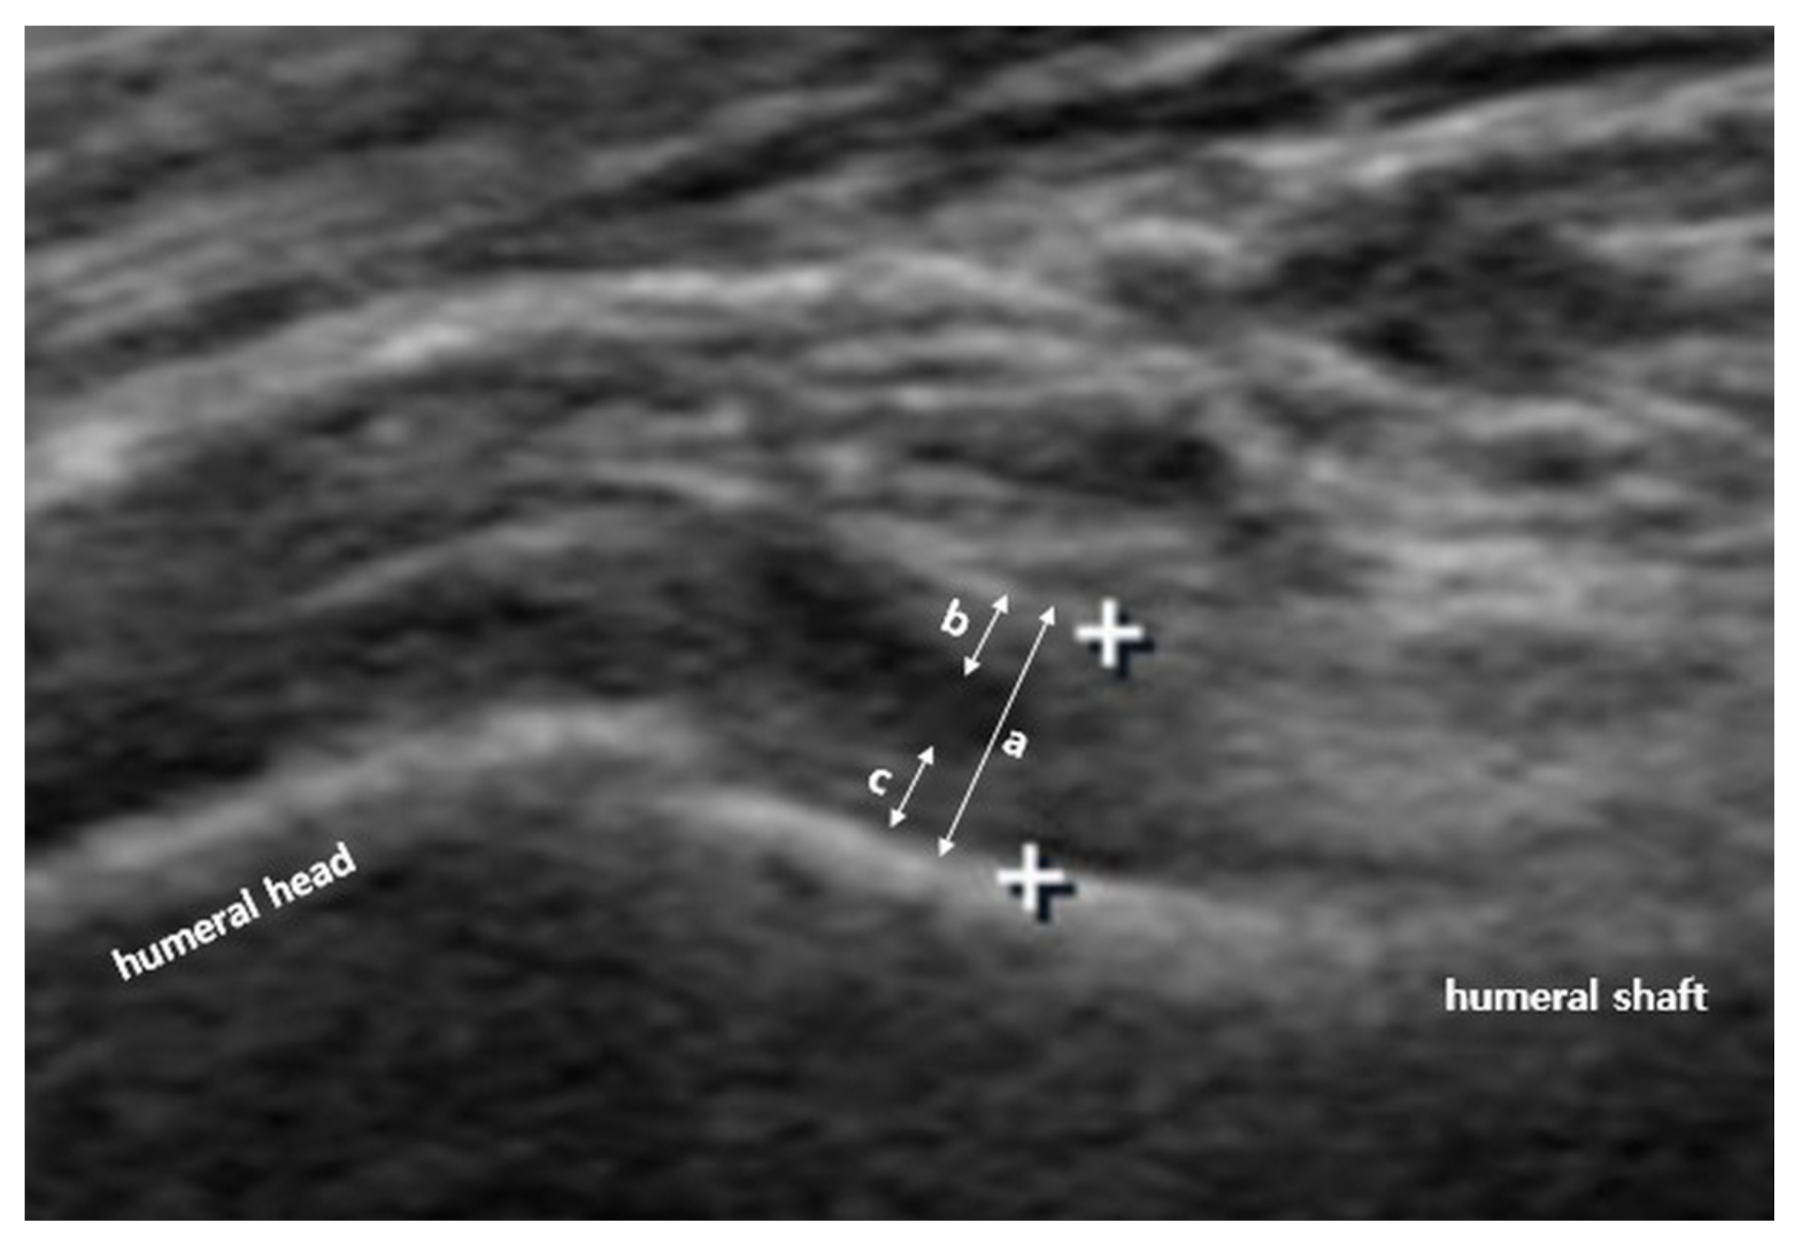

2.2. Us Protocol and Arm Positions